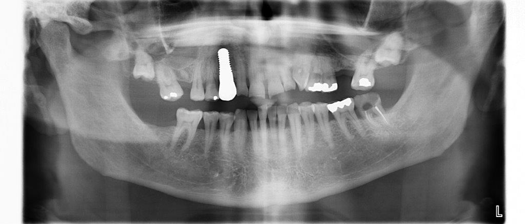

Fig 10. Preoperative panoramic radiograph.

Figure 10

Figure 10 through Figure 13 show the preoperative x-ray and the sequence of beginning with healed sites through the surgical placement of the implants. The implants were protected by an Essix-style wound-protection removable retainer for approximately 12 weeks. After the integration phase, the implants and the natural dentition were prepared using traditional crown-and-bridge high-speed diamond and zirconia cutting burs to remove decay and existing restorative materials, to complete and refine the natural-tooth structures to receive full-crown coverage, and to prepare and refine gingival margins of the zirconia implants where needed.